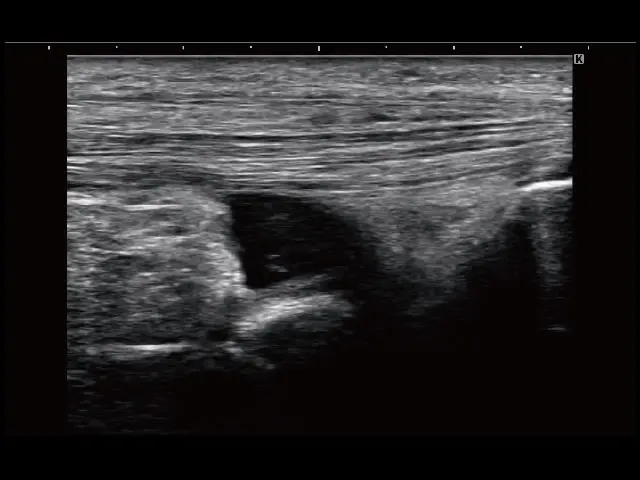

イメージギャラリー

イメージ画像を表示する